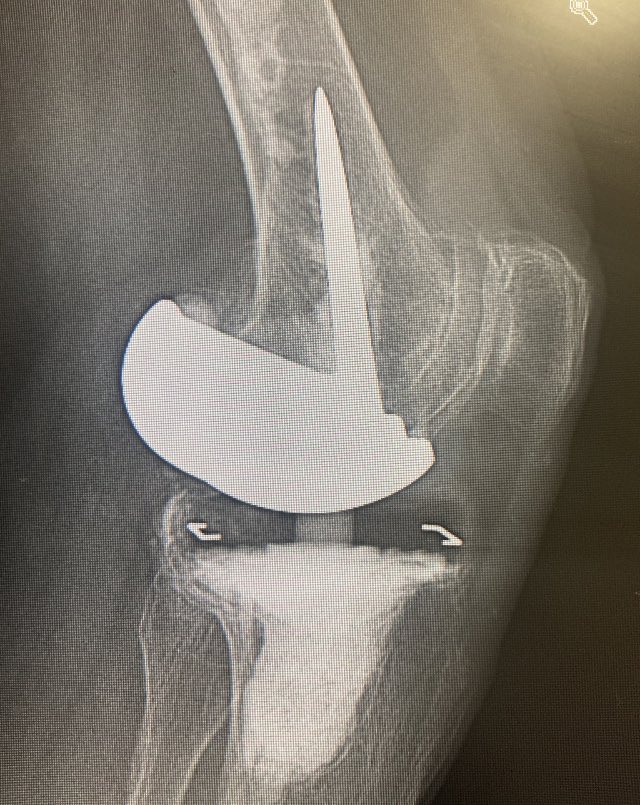

#OurWomanMentors arranca en Madrid el evento de #community dirigido al #liderazgo en traumatología. Coaching y magia para seguir creciendo. @AO_spain

Traumatology & https://t.co/mnYM2D4KUJ